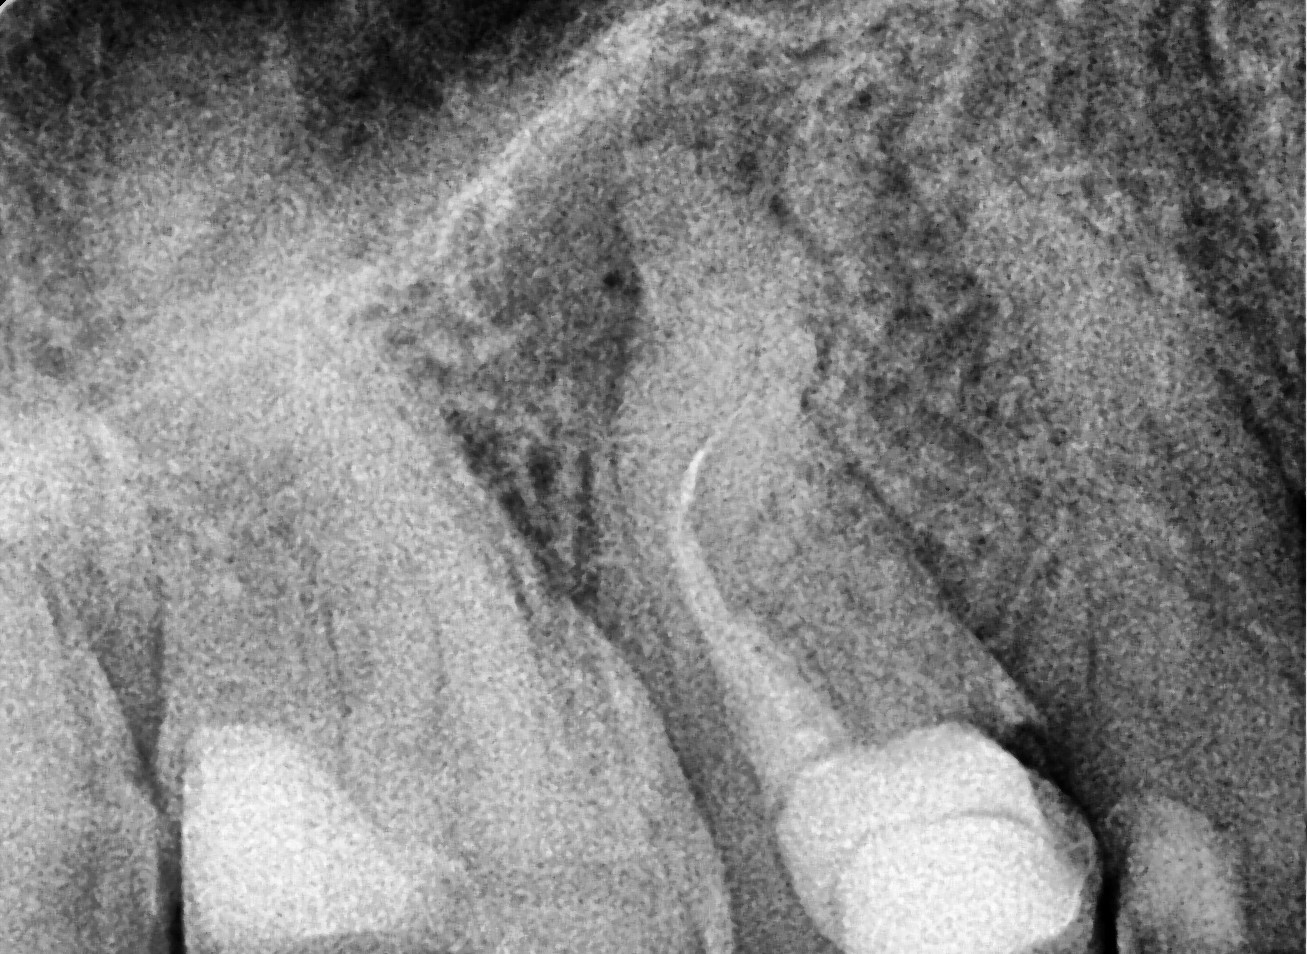

Clinical and radiographic examination revealed a short root filling and the presence of fractured instruments (image 1).